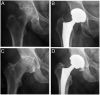

Acetabular component orientation and position are important factors in the short- and long-term outcomes of total hip arthroplasty. Different definitions of inclination and anteversion are used in the orthopaedic literature and surgeons should be aware of these differences and understand their relationships. There is no universal safe zone. Preoperative planning should be used to determine the optimum position and orientation of the cup and assess spinopelvic characteristics to adjust cup orientation accordingly. A peripheral reaming technique leads to a more accurate restoration of the centre of rotation with less variability compared with a standard reaming technique. Several intraoperative landmarks can be used to control the version of the cup, the most commonly used and studied is the transverse acetabular ligament. The use of an inclinometer reduces the variability associated with the use of freehand or mechanical alignment guides.